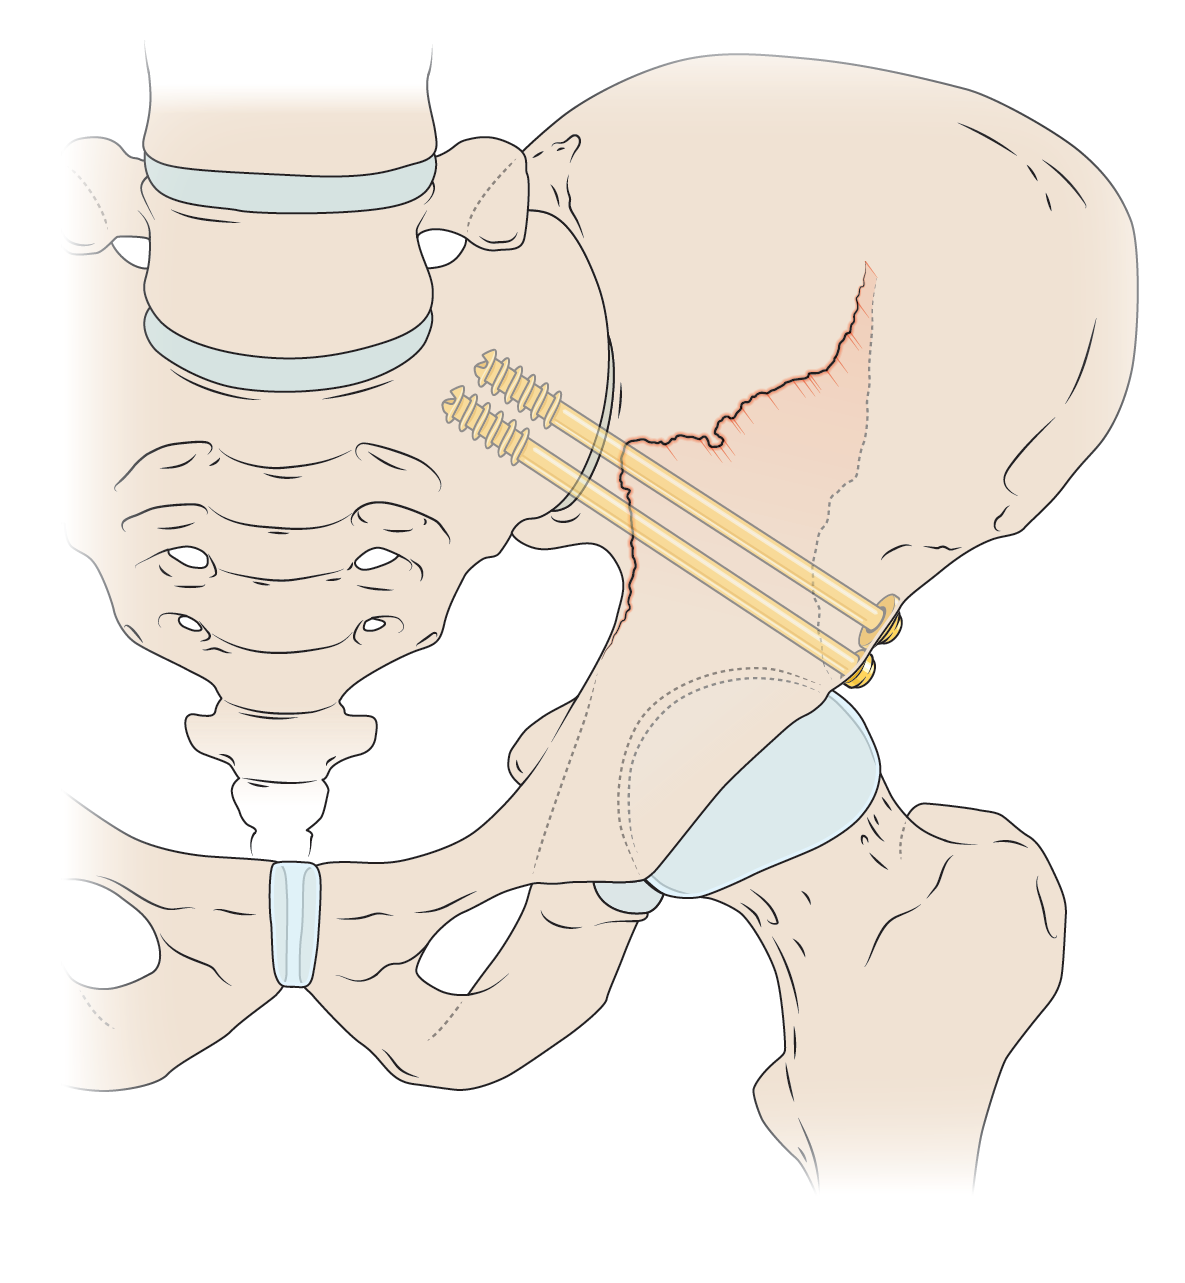

Medical Illustration

All images are works made for hire and are the exclusive property of the client. These are shown as sample purposes of my work only. For licensable work, please see my Illustration Services page.

Contract freelancer for many others, some examples of my work below.